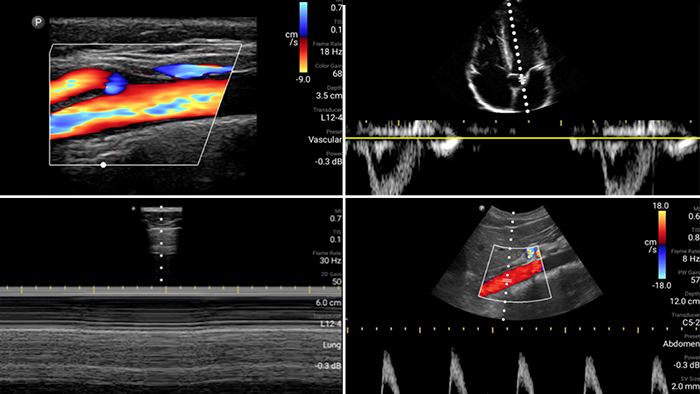

Lumify is with you

every step of the way

Evaluate, diagnose and treat your patients in

minutes with a multi-point POCUS exam.

Broadband linear array transducer

Lumify L12-4 broadband linear array transducer

• 12 to 4 MHz extended operating frequency range

• Aperture size: 34mm

• 2D, steerable color Doppler, M-mode, advancedXRES and multivariate harmonic imaging, SonoCT

• High resolution imaging for shallow applications: soft tissue, vascular, superficial, musculoskeletal and lung

• Center line marker

• USB-C transducer with replaceable cable